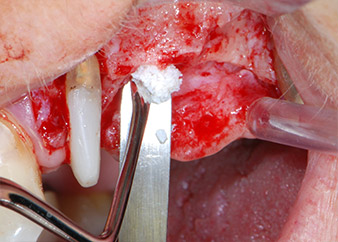

Knochendefizite an der mesialen Fläche des Zahns 27 und an der bukkalen Wurzel des Zahns 24 wurden mit xenogenem Knochenersatzmaterial aufgefüllt und mit einer resorbierbaren Kollagenmembran (Geistlich Bio-Gide) im Sinne einer GBR-Augmentation (Abb. 13 und 14) abgedeckt.

Xenogenes Knochenersatzmaterial

Abb. 13: Xenogenes Knochenersatzmaterial wird zur Auffüllung der verbleibenden Knochendefekte verwendet ...

resorbierbares Kollagenmembran

Abb. 14: ... und mit einer resorbierbaren Kollagenmembran abgedeckt. Die grau-rosa-farbene Struktur zwischen den Elevatorien am oberen Bildrand ist gingivales Papillengewebe.